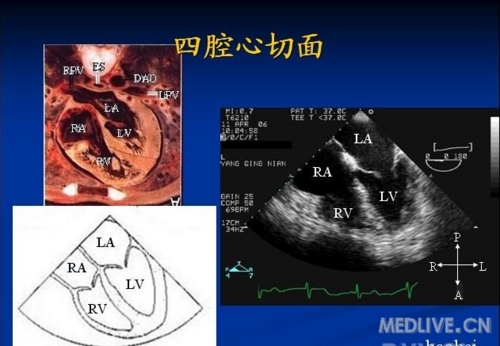

经食道超声心动图常用标准切面

如图,二维超声心动图中,此为____________切面.